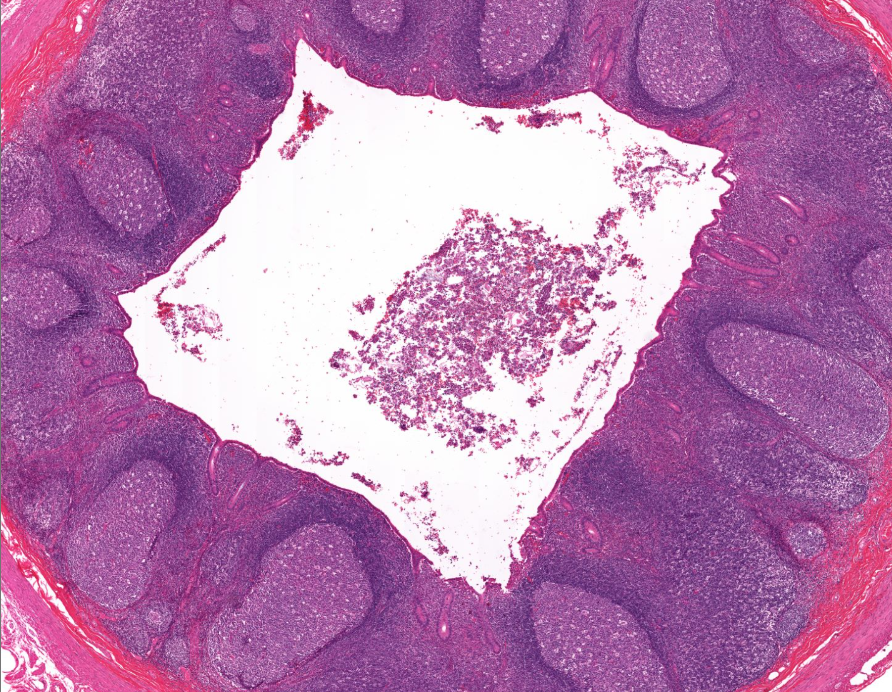

vermiform appendix

notice the absurd amount of lymphocytes

no villi